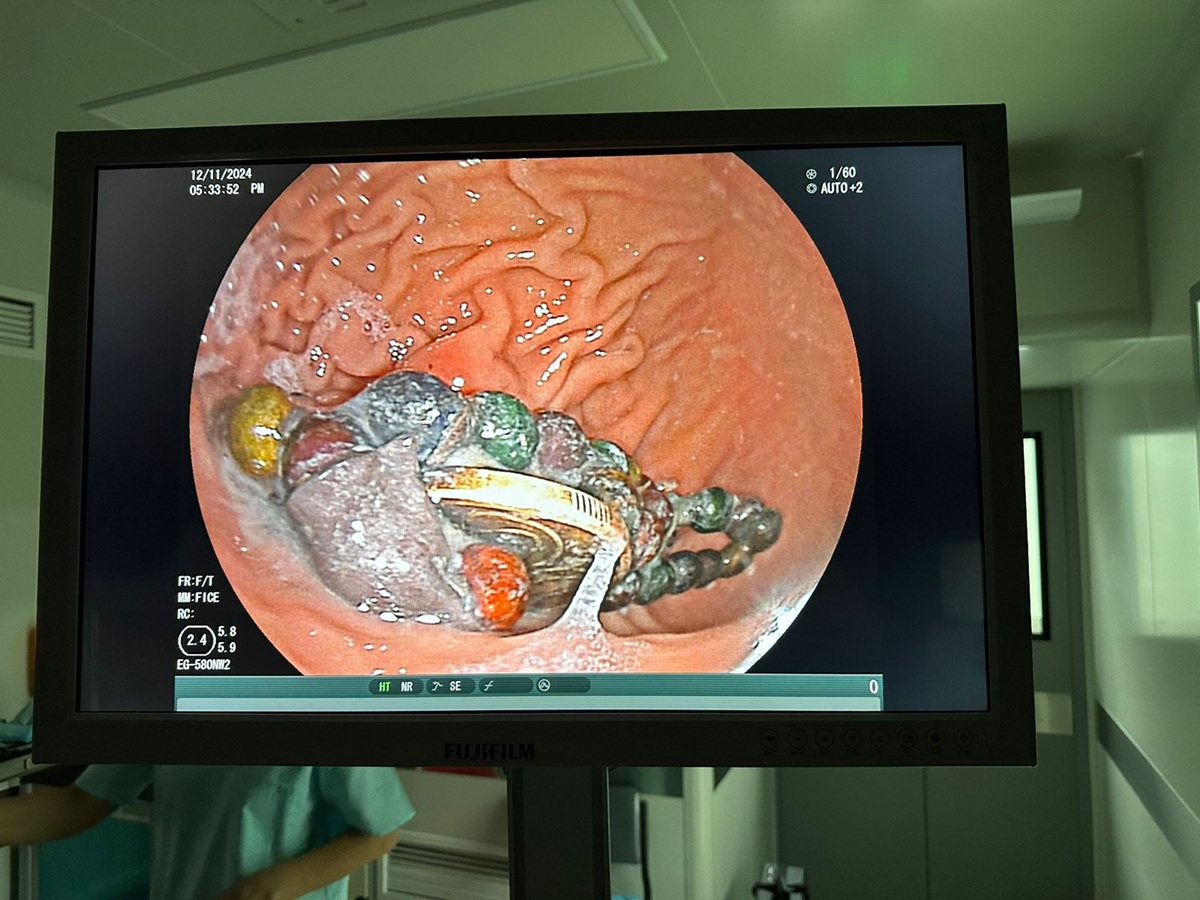

Во время процедуры эндоскописты Роллан Елеусинов и Нуржигит Жансултан сразу же обнаружили семечку и успешно извлекли ее из бронхов.

Он отметил, что чаще всего приходится извлекать монеты, а также батарейки, магниты.

Магнитики особенно опасны, они могут попасть в тонкую кишку и желудок, вызывая перфорацию (разрыв кишечника). К счастью, пока ни у кого не было осложнений, все магниты успешно удалялись. У нас большой опыт, мы закупаем много инструментов. Когда ездим на конференции в Дубай, Корею, Китай, на свои средства закупаем инструменты и развиваемся. По Казахстану мы одни из лидеров по операциям по удалению инородных тел, - рассказал Роллан Елеусинов.